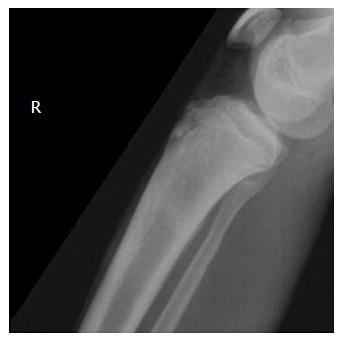

运动中的应力性骨折正变得越来越常见,占所有运动损伤的10%。此类损伤约90%位于下肢。本文旨在确定运动员下肢应力性骨折的最佳管理方法,以提高恢复率并缩短重返运动的时间。这种情况的治疗计划因损伤部位而异。然而,应力性骨折仍明显分为“高”风险和“低”风险。“低风险”应力性骨折是指骨折扩展、延迟愈合或不愈合概率较低的骨折,因此通过休息和限制运动即可可靠地进行处理。这些包括胫骨干后内侧、跖骨干、腓骨远端、股骨颈内侧、股骨干和跟骨的应力性骨折。相比之下,“高风险”应力性骨折的骨折扩展、移位、延迟愈合和不愈合发生率更高,因此需要立即停止活动,并转诊至骨科,以评估是否需要手术干预。这些包括胫骨干前侧、第五跖骨基底、内踝、股骨颈外侧、舟骨和拇趾籽骨的应力性骨折。为了确定管理这些损伤的最佳方法,我们展示并回顾了指导运动员应力性骨折治疗的现有证据。据此,我们注意到某些高风险应力性骨折的手术管理在缩短重返运动时间和提高恢复率方面的作用有所增加。在此之后,针对运动员常见应力性骨折类型的管理提供了关键建议。还给出了五个病例报告,以说明以运动为重点的下肢应力性骨折治疗在临床中的应用。

Stress fractures of the femoral neck in runners: a review.跑步者股骨颈的应力性骨折:综述。

Res Sports Med. 2016 Jul-Sep;24(3):185-99. doi: 10.1080/15438627.2016.1191489. Epub 2016 Jun 6.